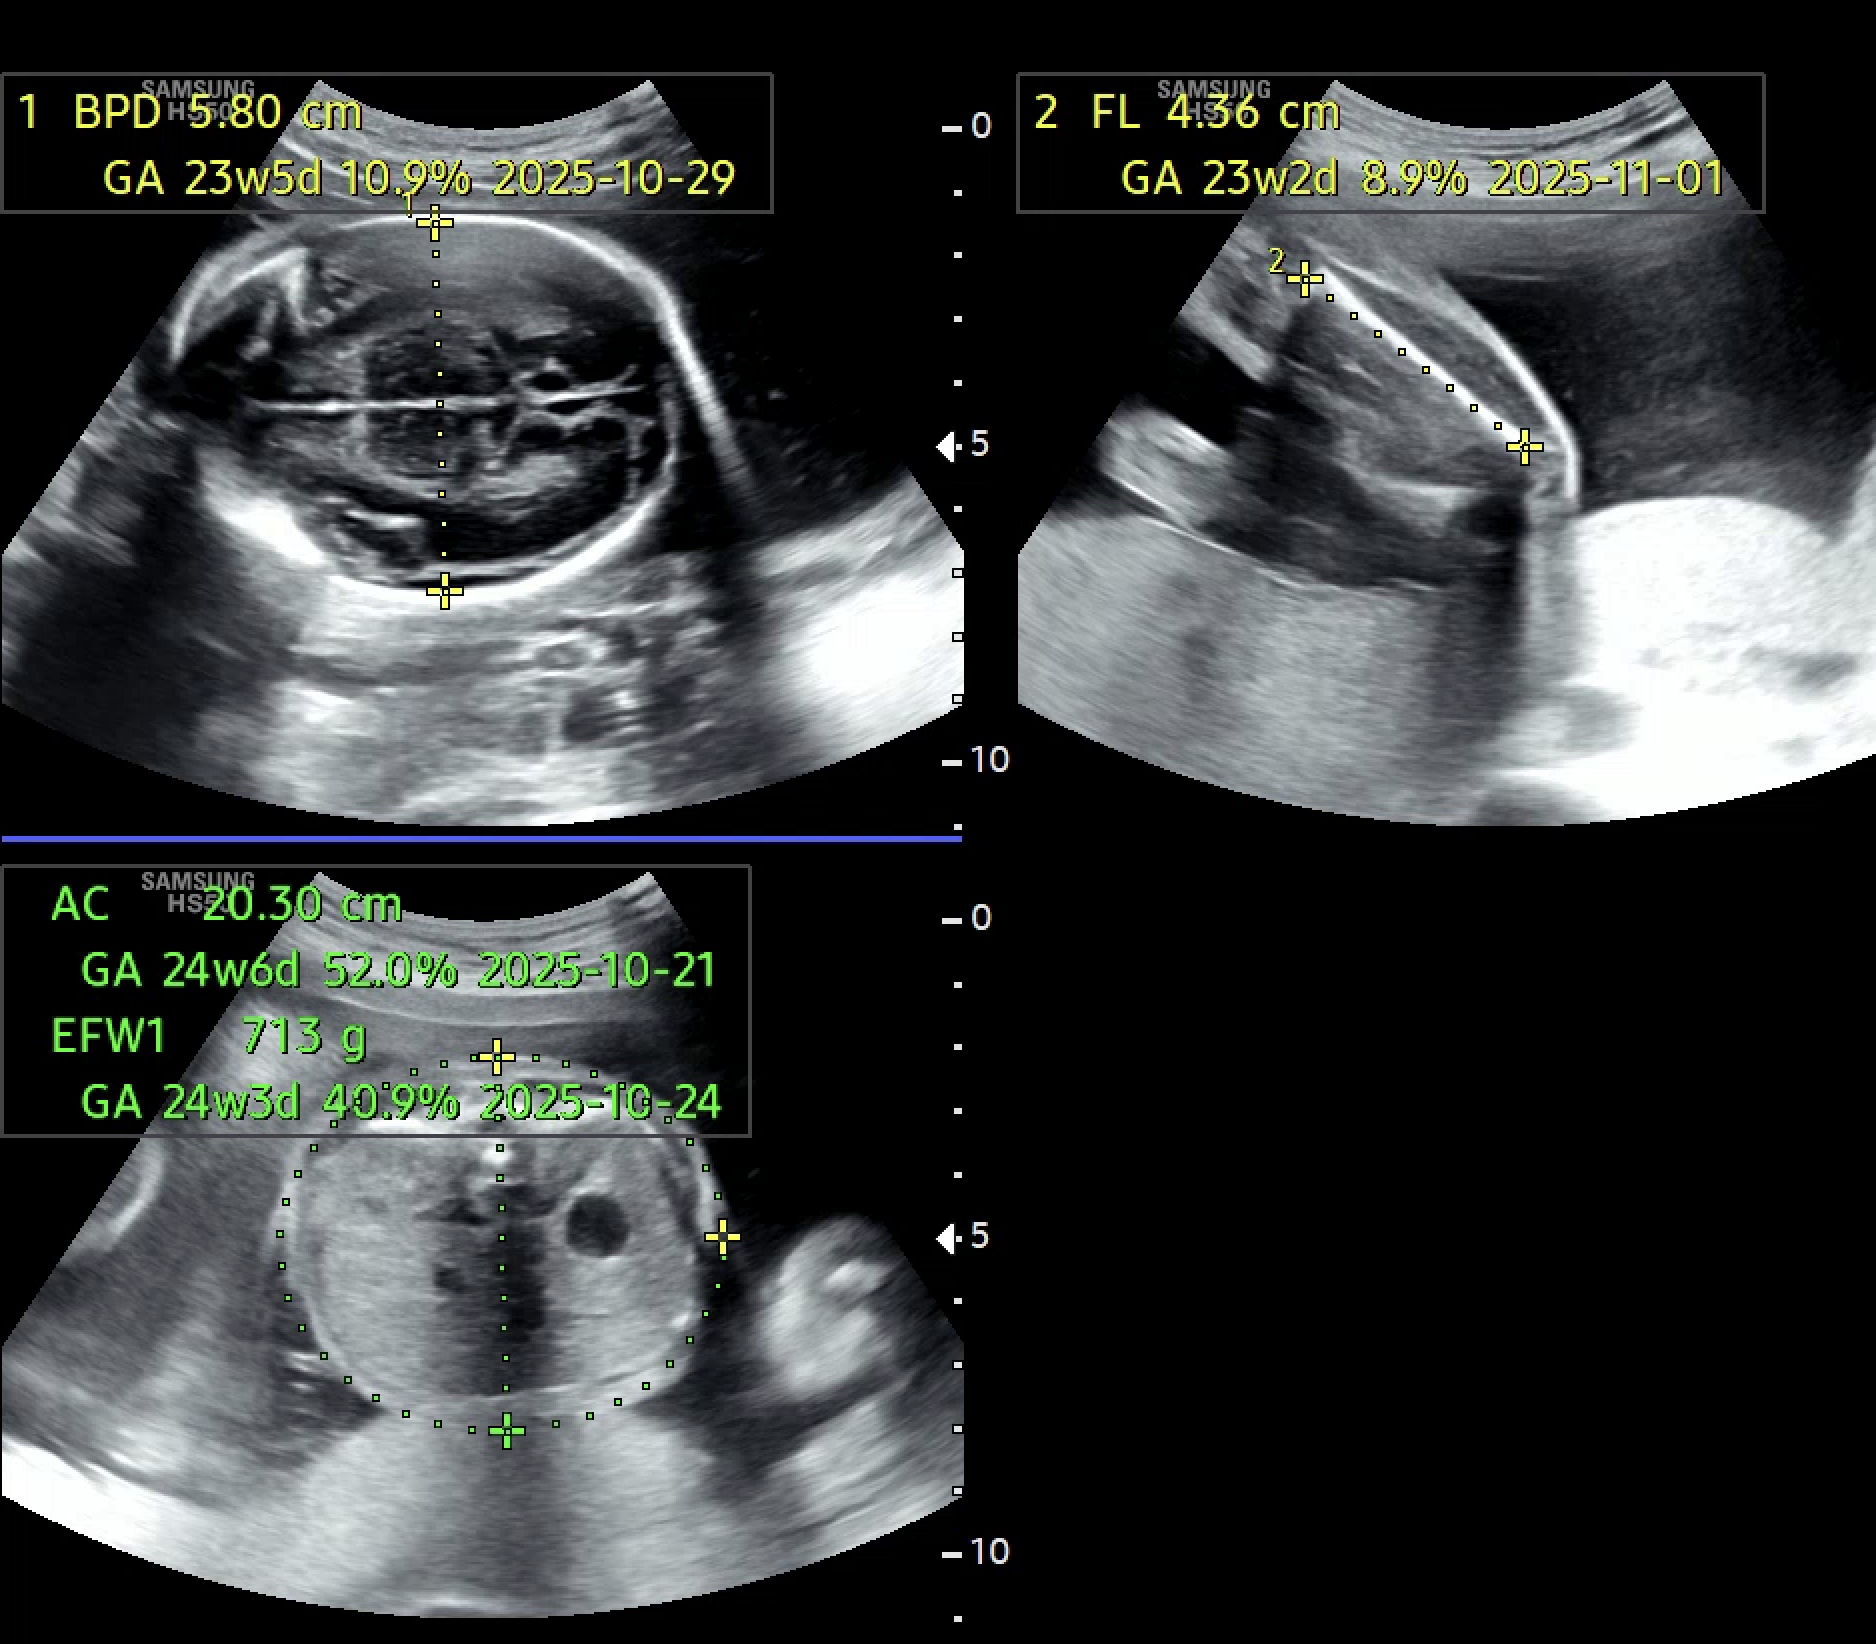

모델이 더 안정적으로 학습하려면 초반부터 모든 데이터를 학습에 사용하고, 확신이 없는 데이터까지 포함하도록 변경했다. 하지만 무엇보다도, 초음파 이미지라는 특성상 한 장의 이미지에 여러 부위가 함께 측정되는 경우도 많다는 사실을 간과하고 있었다. 실제 의료진도 하나의 이미지에서 AC, FL 등 여러 부위를 동시에 측정한다. 하지만 softmax 기반의 멀티 클래스 분류 방식은 무조건 하나의 클래스만 선택해야 하기 때문에, 이런 현실적인 상황을 반영하지 못했다. 결과적으로, 데이터 자체는 멀티 클래스 특성을 가지고 있는데, 모델은 억지로 싱글 클래스로 억지로 해석하고 있었다.

아래는 멀티 클래스 기반으로 변경한 뒤의 실제 예측 결과 예시이다. 단일 클래스 방식에서는 하나의 부위만 예측되던 이미지에서, 이제는 여러 부위가 동시에 높은 확률로 예측되는 모습을 확인할 수 있다.